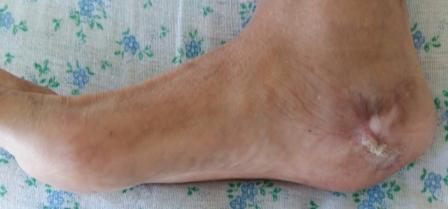

Уважаемые коллеги. Вчера госпитализирован пациент 1970г.р. , в ноябре 2014г, получил о/перелом пяточной кости. в другой клинике произведена КДО аппаратом Илизарова, после трех месяцев аппарат сняли? , и больной начал наступать и ходить?- все это со слов б-ного(р-снимков нет.), Жалобы боли при ходьбе к-рая в динамике усиливается, об-но: деформация пяточной кости, движение в г/стоп.суставе почти в польном обьеме, по мед.поверхности пятки рубец плотно спаянный с костью. Предварительный план: корригируюшая остеотомия пяточной кости, для создания свода стопы.( сможем ли опустить бугра пяточной кости из-за натяжения ахиллово сухожилия), и подтаранный артродез. С уважением Абдурашид.

Уважаемые коллеги. Операция была произведена 22.01.16г., только сегодня имеется возможность отправить. L-образный доступ. . при ревизии подтаранный сустав сохранен, поэтому линейная остеотомия, подкожная ахиллотомия. Подготовка ложа, и смещенный отломок спущен вниз к ложу , но до конца не смогли. Фиксирован двумя винтами. По медиальной поверхности рубец плотно спаянный с костным осколком, пока не трогали из-за опасения инфицирования, после заживления раны потом будем думать, что делать.